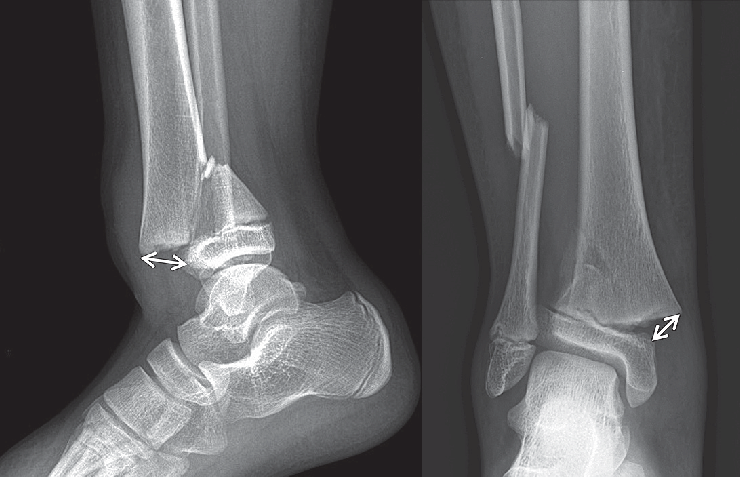

Qu’est-ce qu’une plaque de verrouillage tibial distal médial ?

Les rayons X sont couramment utilisés pour évaluer les fractures et évaluer le degré de déplacement et d'instabilité.Des études d'imagerie supplémentaires, telles que des tomodensitogrammes ou des IRM, peuvent être recommandées pour obtenir des informations plus détaillées sur le modèle de fracture, l'atteinte des tissus mous et la qualité osseuse.